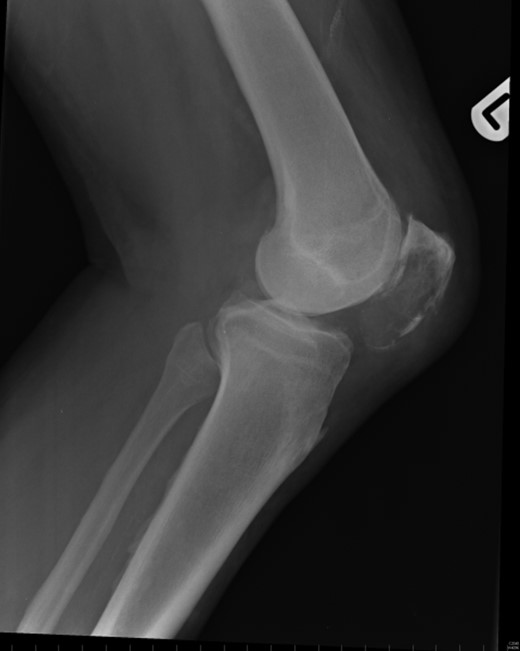

Nineteen months earlier the patient had consulted his general practitioner complaining of left knee pain. Radiographs performed at that time were reported to show joint space narrowing within the patello-femoral compartment as well as early joint space narrowing within the medial compartment. A subchondral lucency was also noted within the patella which was described as a subarticular cyst secondary to the previously mentioned patello-femoral degeneration (Figs 1–3).

The absence of associated features of systemic disease, as well as radiographic appearances in keeping with early patello-femoral osteoarthritis (OA), account for the delay in diagnosis. The initial images suggest mild degeneration but, whilst subarticular cysts are a radiographic feature of OA, the lesion shown in this case is larger than would be expected with the level of disease shown elsewhere in the joint.